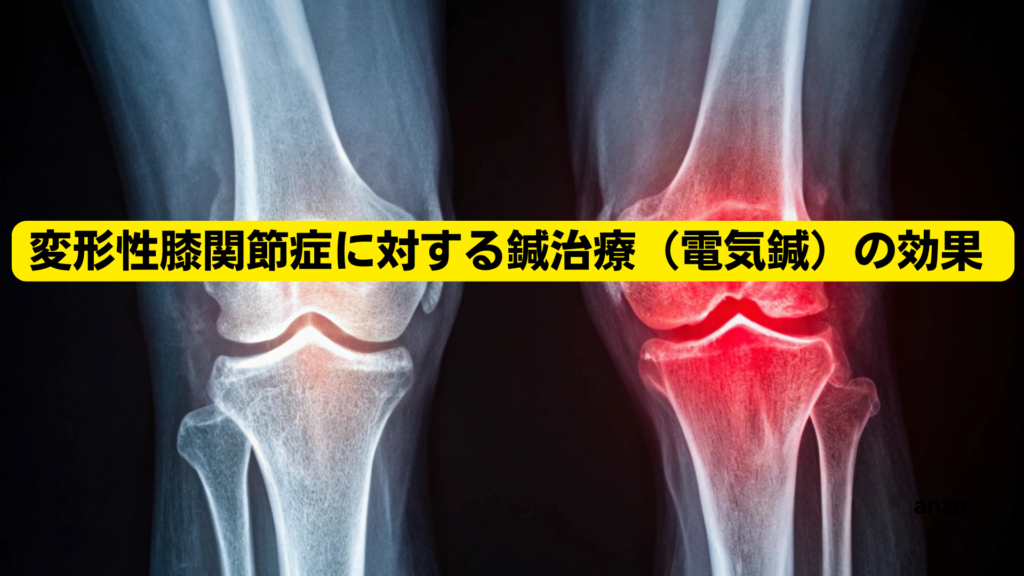

変形性膝関節症に対する鍼治療(電気鍼)の効果 |福岡県筑紫野市二日市

こんにちは!福岡県筑紫野市二日市にある杏鍼灸整骨院の陣内由彦です。 膝の痛みで日常生活に困っている方は、とても多くいらっしゃいます。 特に50歳以上の方では、変形性膝関節症という症状に悩まされている方が少なくありません。 実は日本では、症状が... -